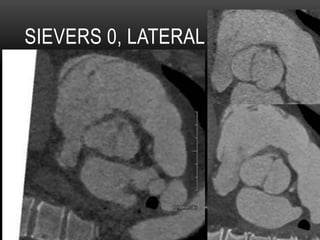

SIEVERS CLASSIFICATION OF BAV

SIEVERS 0, LATERAL

SIEVERS 1, L-R

Hallett RL, et al. Curr Radiol Rep (2016) 4:1-14

DIASTOLE SYSTOLE